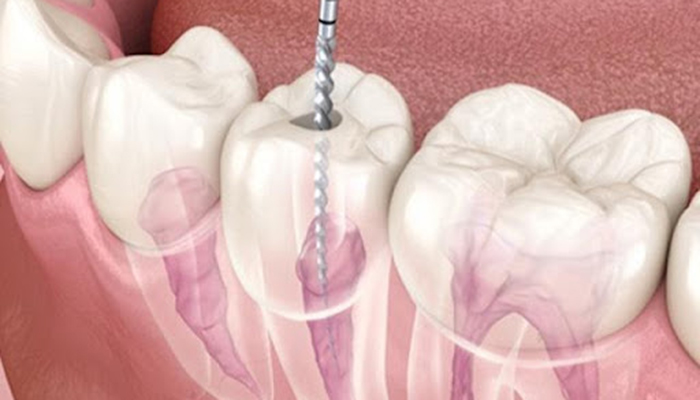

根管治療の具体的な治療内容

歯の根っこ(神経)の中から痛みや腫れの原因である「感染した汚染物」を、取り除く治療です。

針のような道具を使って、感染した汚染物をとりのぞいていきます。

汚れを取り除いた箇所をキレイに清掃・消毒して、お薬で埋めるまでが根管治療です。